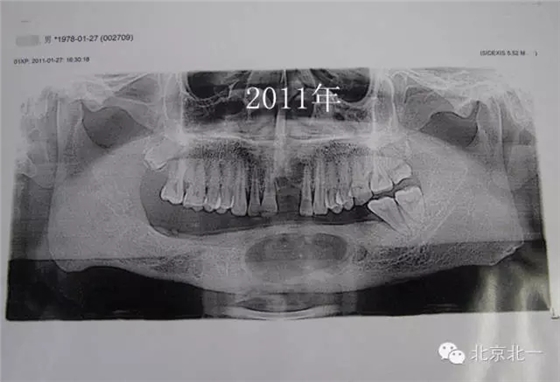

患者男,33歲,左下頜囊腫復(fù)發(fā)兩次就診。

圖三、再次手術(shù)后第二次復(fù)發(fā)